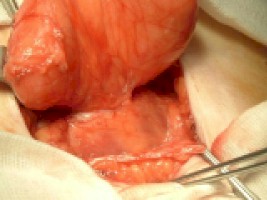

3c. Disección del cuello de la hernia

3d. Apertura del saco y extirpación del mismo si se puede